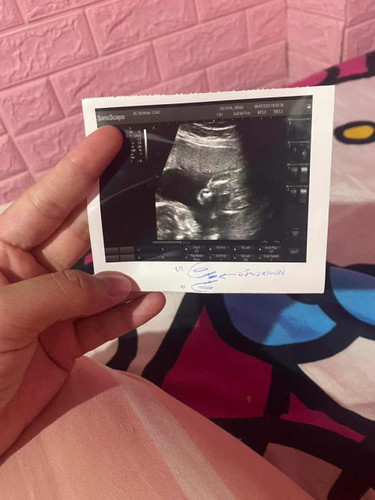

เพศลูก ผญ/ผช

แม่ๆว่าหญิงหรือชายคะ หมอบอกแม่หญิง80%แม่เลยไม่ค่อยแน่ใจ😂#ขอบคุณสำหรับคำตอบค่ะ #ท้องแรกคะ

ลูกสาวค่าาา กลีบชัดมากๆ